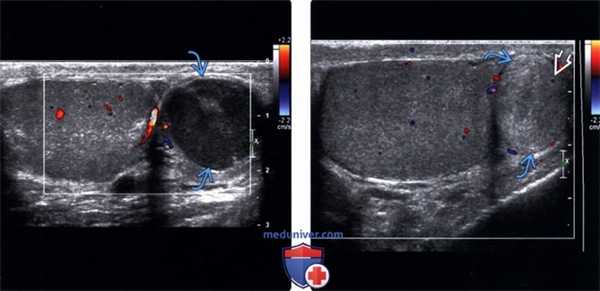

(Слева) У мужчины 41 года внутри пальпируемой гипоэхогенной аденоматозной опухоли, расположенной в хвосте придатка яичка, внутренний кровоток не визуализируется.

(Справа) У мужчины 50 лет в течение пяти лет проводилось ультразвуковое наблюдение за предположительно аденоматозной опухолью яичка. Представленное объемное образование овальной формы с четкими конкурами в хвосте придатка яичка является изоэхопенным по отношению к ткани яичка, также наблюдается минимальный внутренний кровоток. Обратите внимание на значительное различие эхогенности по сравнению с аналогичной опухолью, показанной у предыдущего пациента.

(Слева) Представленная гиперэхогенная аденоматозная опухоль овальной формы в хвосте придатка яичка была обнаружена у мужчины 37 лет случайно.

(Справа) Представленная аденоматозная опухоль белочной оболочки была случайно обнаружена у мальчика 12 лет на МРТ тазовой области. Опухолевый очаг является одновременно эндофитным и экзофитным по отношению к яичку, поскольку сосредоточен в его белочной оболочке. Обратите внимание на минимальный внутренний кровоток.